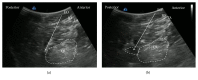

Purpose of Review. Since the original publication on the quadratus lumborum (QL) block, the technique has evolved significantly during the last decade. This review highlights recent advances in various approaches for administering the QL block and proposes directions for future research. Recent Findings. The QL block findings continue to become clearer. We now understand that the QL block has several approach methods (anterior, lateral, posterior, and intramuscular) and the spread of local anesthetic varies with each approach. In particular, dye injected using the anterior QL block approach spread to the L1, L2, and L3 nerve roots and within psoas major and QL muscles. Summary. The QL block is an effective analgesic tool for abdominal surgery. However, the best approach is yet to be determined. Therefore, the anesthetic spread of the several QL blocks must be made clear.